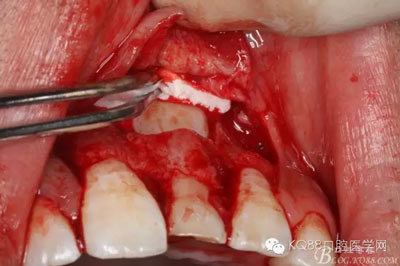

圖14.牙冠周圍滲血多,無法粘結(jié)托槽。位置也高,隨與家屬溝通,暫時保留乳Ⅰ。待21初步穩(wěn)定,再考慮正畸牽引

圖15.輕輕的把21牙冠牽引至乳Ⅰ根尖方向,并擺正牙冠位置。(拔苗助長)

圖16.牙冠上方覆蓋膠原蛋白膜

圖17.骨壁重新覆蓋回去